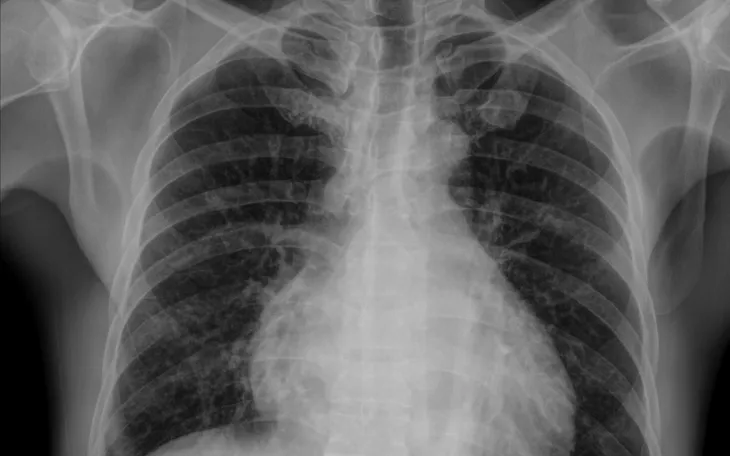

Trường hợp bệnh nhân C.Đ.C. (52 tuổi, Phú Thọ) nhập Bệnh viện Bạch Mai vì chảy máu mũi kéo dài. Trong quá trình điều trị bạch cầu cấp dòng tủy, người bệnh được truyền huyết tương và sau khoảng 20 phút, xuất hiện khó thở, SpO2 giảm, nghe phổi có ran ẩm hai bên. Kết quả chụp CT cho thấy phù phổi cấp, được xác định là quá tải tuần hoàn liên quan truyền máu (TACO). Bệnh nhân được xử trí kịp thời và cải thiện.

Các nghiên cứu quốc tế cho thấy biến chứng phổi sau truyền máu không hề hiếm. Tại Bệnh viện Đại học California (2012-2022), trong hơn 573.000 lượt truyền, có 102 ca TACO, tương đương 1/500 người truyền. CDC Hoa Kỳ ước tính tần suất TACO từ 1-11% tùy nhóm bệnh nhân.